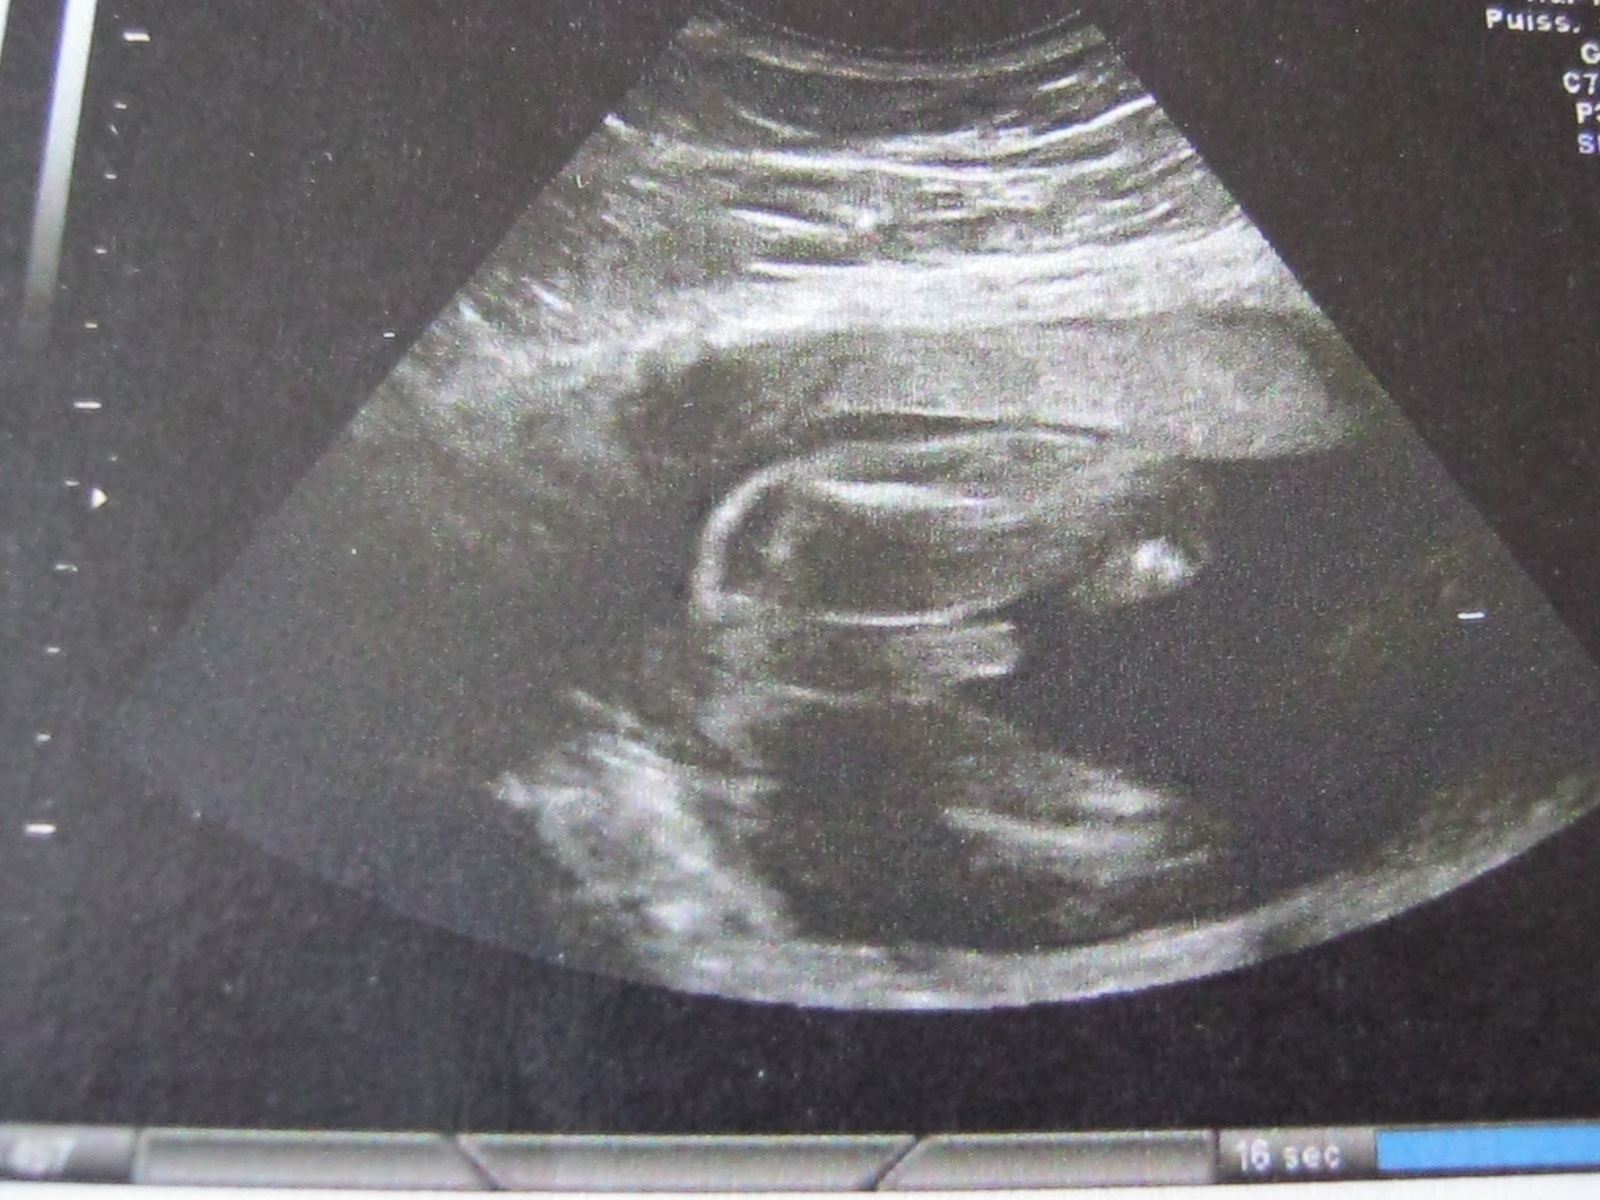

• IMG_0134.JPG

IMG_0134.JPG

376.6 KB · Affichages: 132

c'est.......................................................................... UN PETIT GARCON